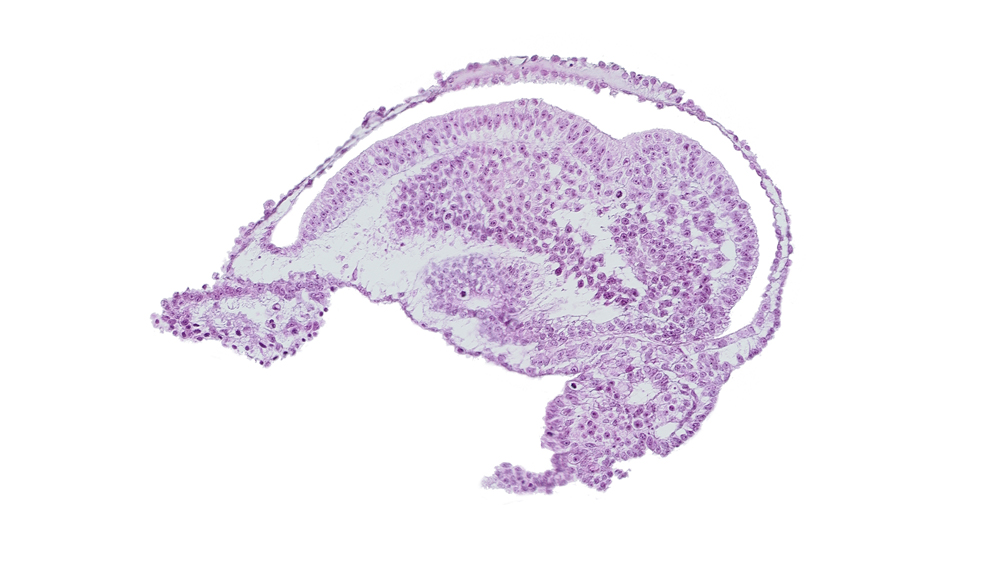

Carnegie Embryo #10157 | Location: 11-03

Keywords: allantoic diverticulum, amnion, amniotic cavity, blood vessel in connecting stalk mesenchyme, cloacal membrane, embryonic ectoderm cut tangentially, embryonic mesoderm, epiblast, extra-embryonic ectoderm, extra-embryonic mesoderm, gastrulation (primitive) groove

Source: The Virtual Human Embryo.